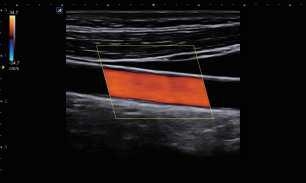

Hệ thống hiệu suất cao

- Nền tảng cấp mô hình hàng đầu

Được trang bị nền tảng cao cấp nhất của Alpinion, E-CUBE 8 Series được trang bị

phần cứng và phần mềm. Độ phân giải, độ tương phản và tính đồng nhất của hình ảnh 2D của nó đã được cải tiến và với việc bổ sung Bộ điều khiển kép, Doppler rõ ràng và chính xác

dữ liệu có thể được hiển thị trong khi vẫn duy trì hình ảnh 2D sắc nét ở Chế độ kết hợp Doppler.